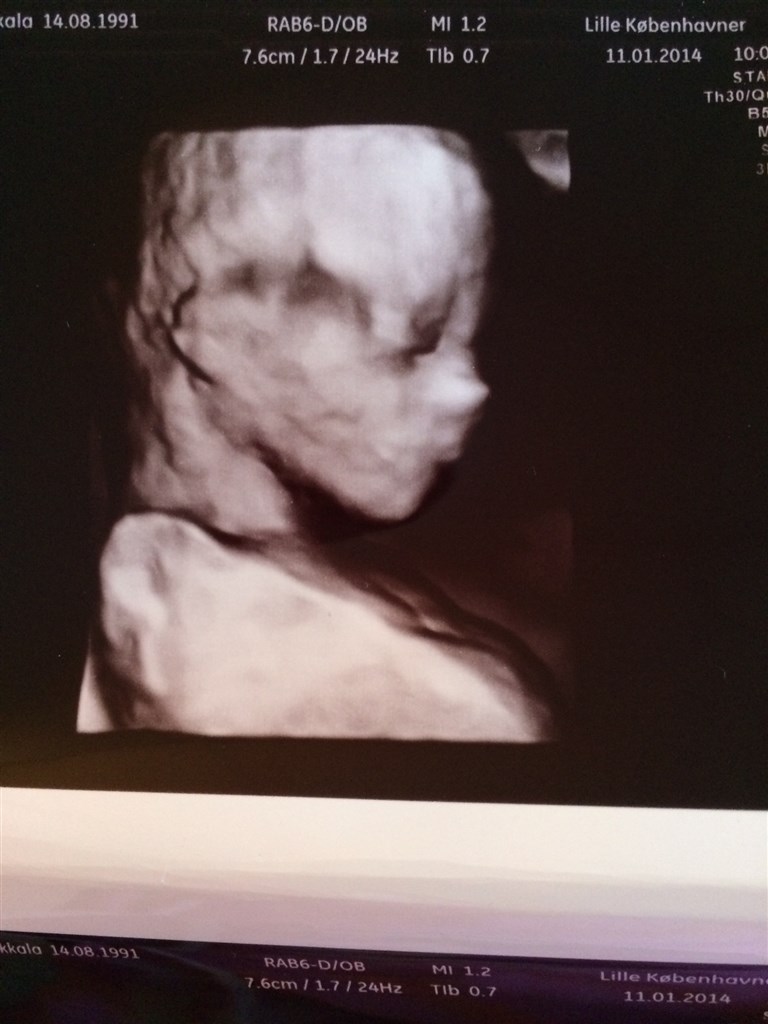

Hvor var det vildt da vi blev scannet, at se prinsessen i 3D  Uge 15+1

vi skal helt sikkert til en 3D scanning i uge 25 denne gang